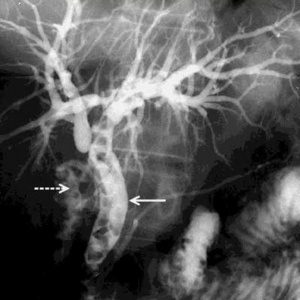

Endoscopic retrograde cholangio pancreatography (ERCP) בשיטה זו מחדירים אנדוסקופ דרך הפה לתריסריון, מזהים את הפפילה על-שם ואטר, ולתוכה מחדירים צנתר שדרכו מזריקים חומר ניגוד לדרכי המרה וללבלב. ההדגמה היא רנטגנית וניתן לראות בה הרחבה של דרכי המרה, אבנים בדרכי המרה (תצלום 30.8) ועוד.

| תצלום 30.8: הדגמת אבנים בדרכי המרה ב- ERCP (חיצים מצביעים על אבנים בדרכי המרה, חץ מקווקו על אבנים בכיס המרה). | |